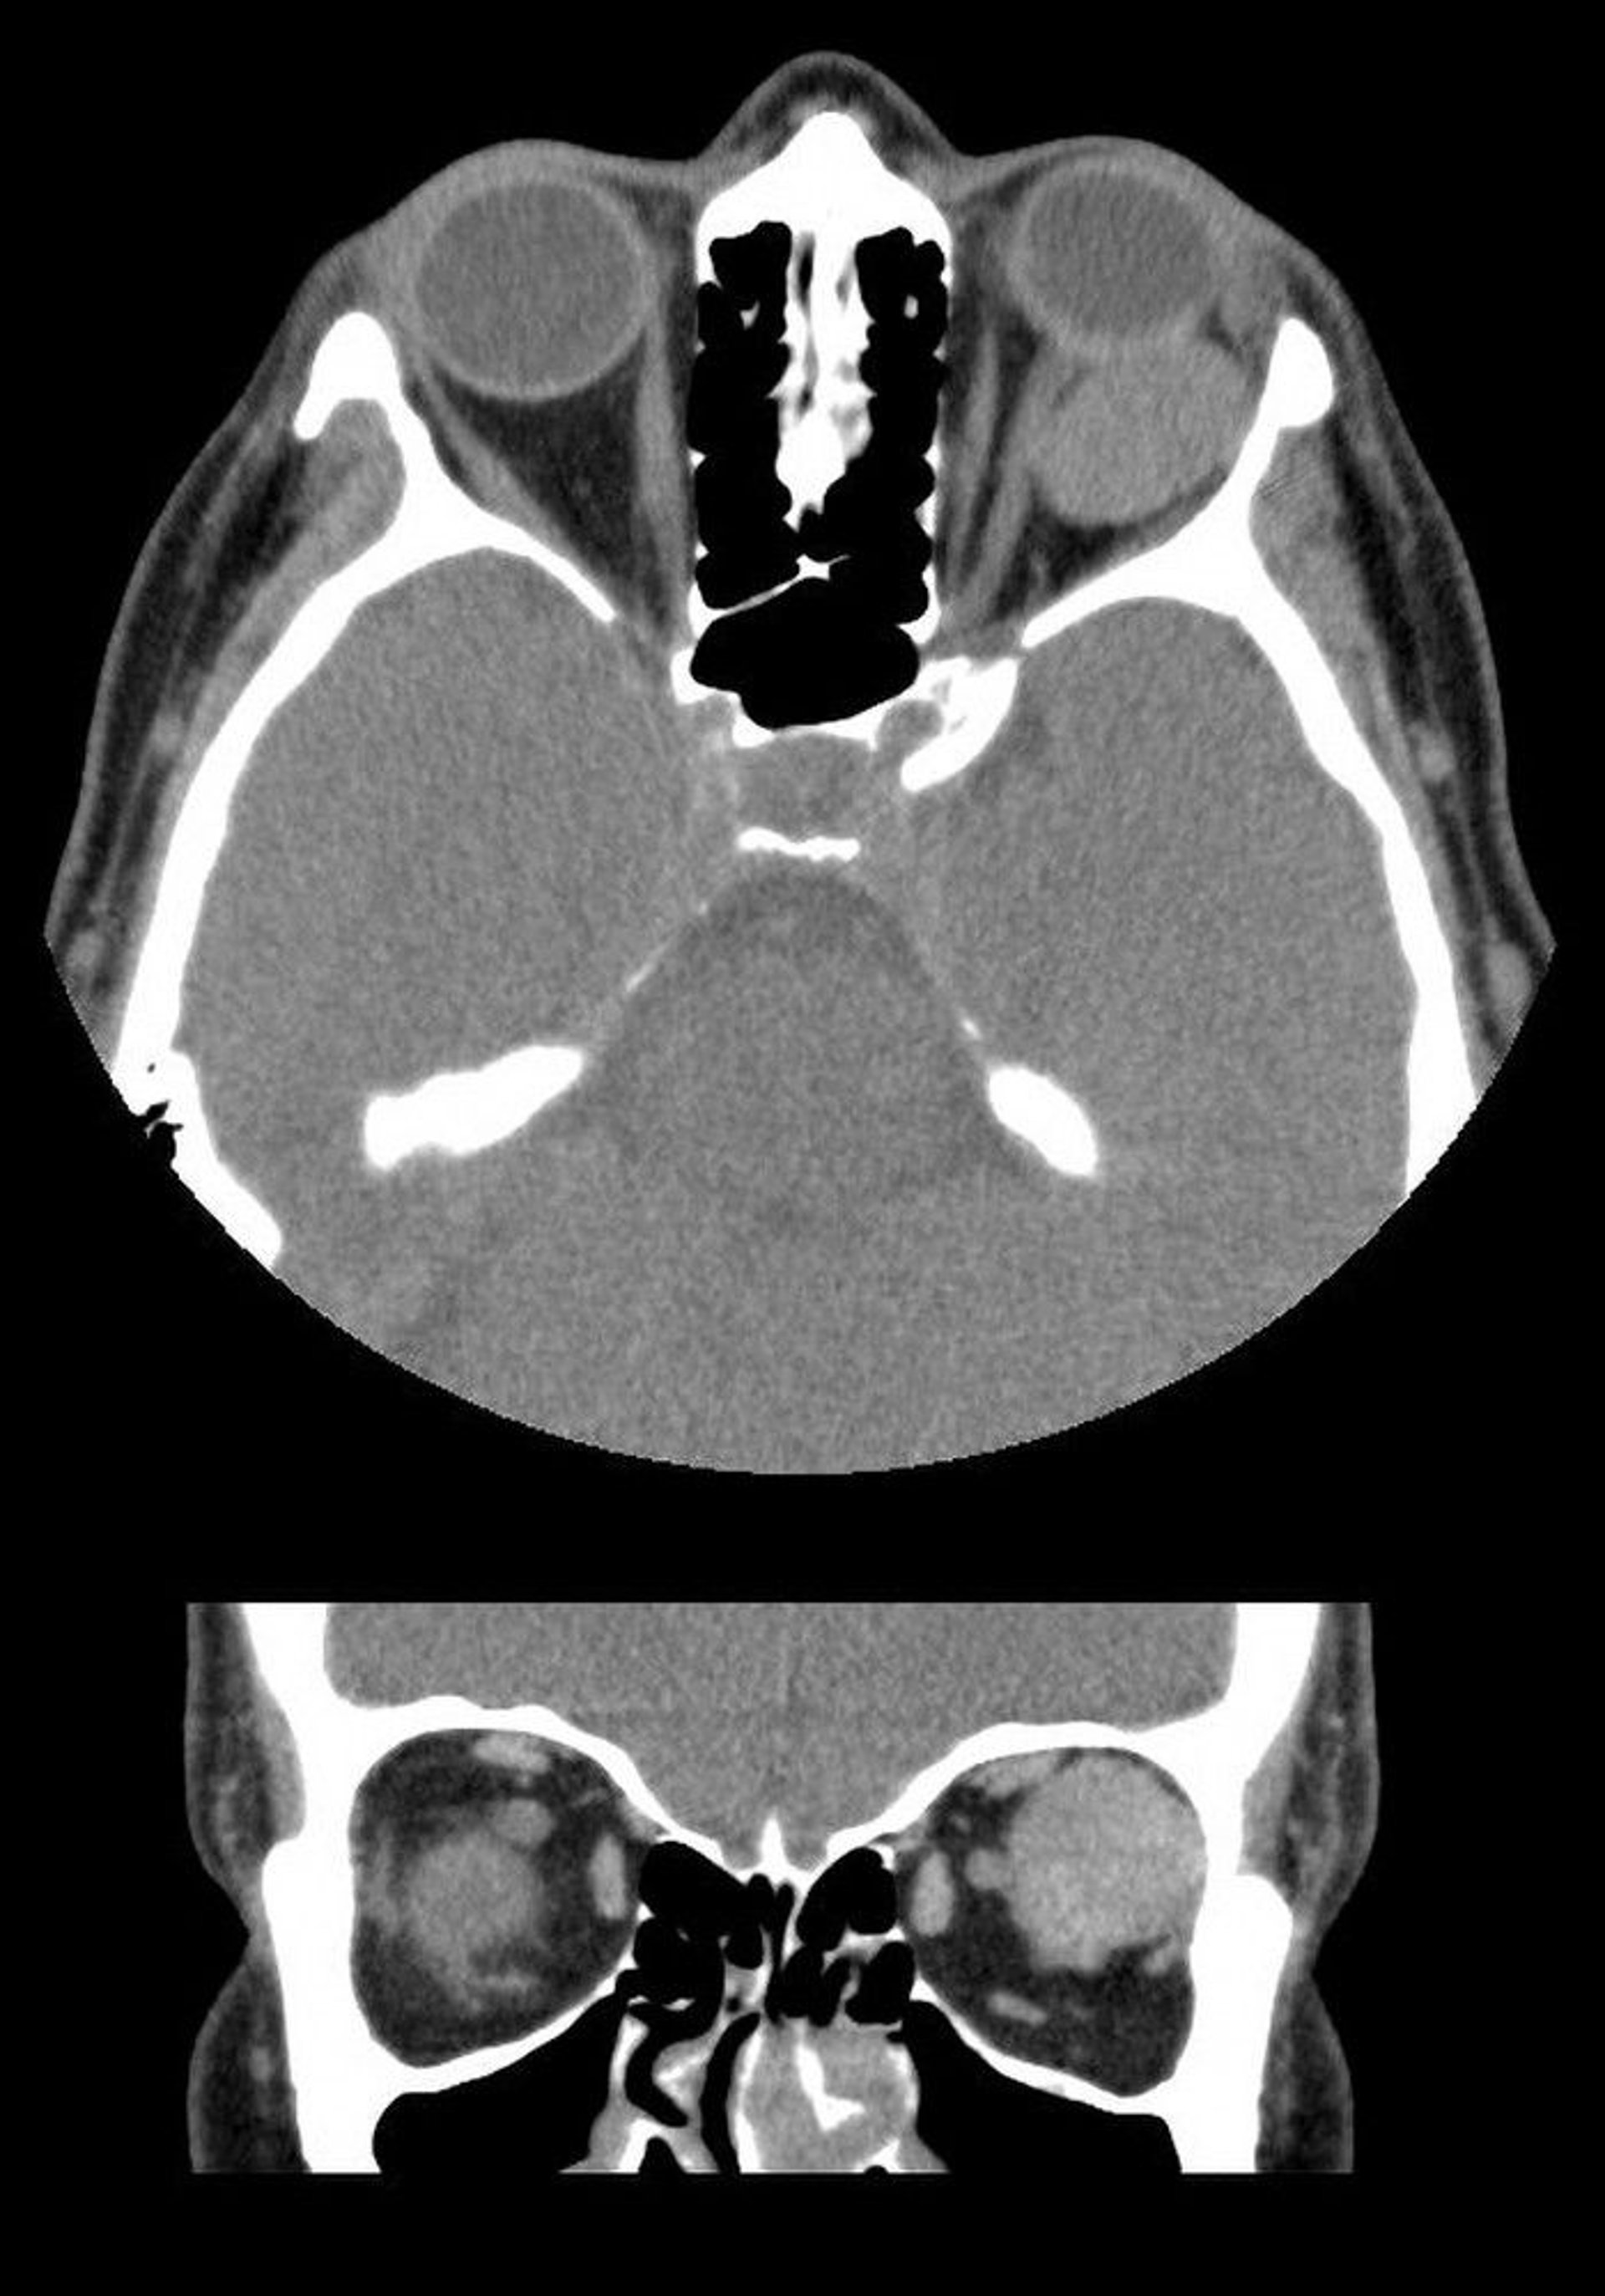

In this image, the axial (top) and coronal (bottom) CT scans show a well-demarcated intraconal mass behind the left globe. The mass is a cavernous venous malformation.

Images courtesy of James Garrity, MD.